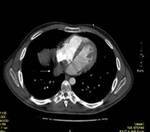

Results: Twenty-two cardiac masses were successfully detected and their characteristics adequately delineated, including eight myxomas, one angiosarcoma, one ventricular lymphoma, one endocardiac metastasis, one epicardiac paraganglioma, and 10 cases of intracardiac thrombi.